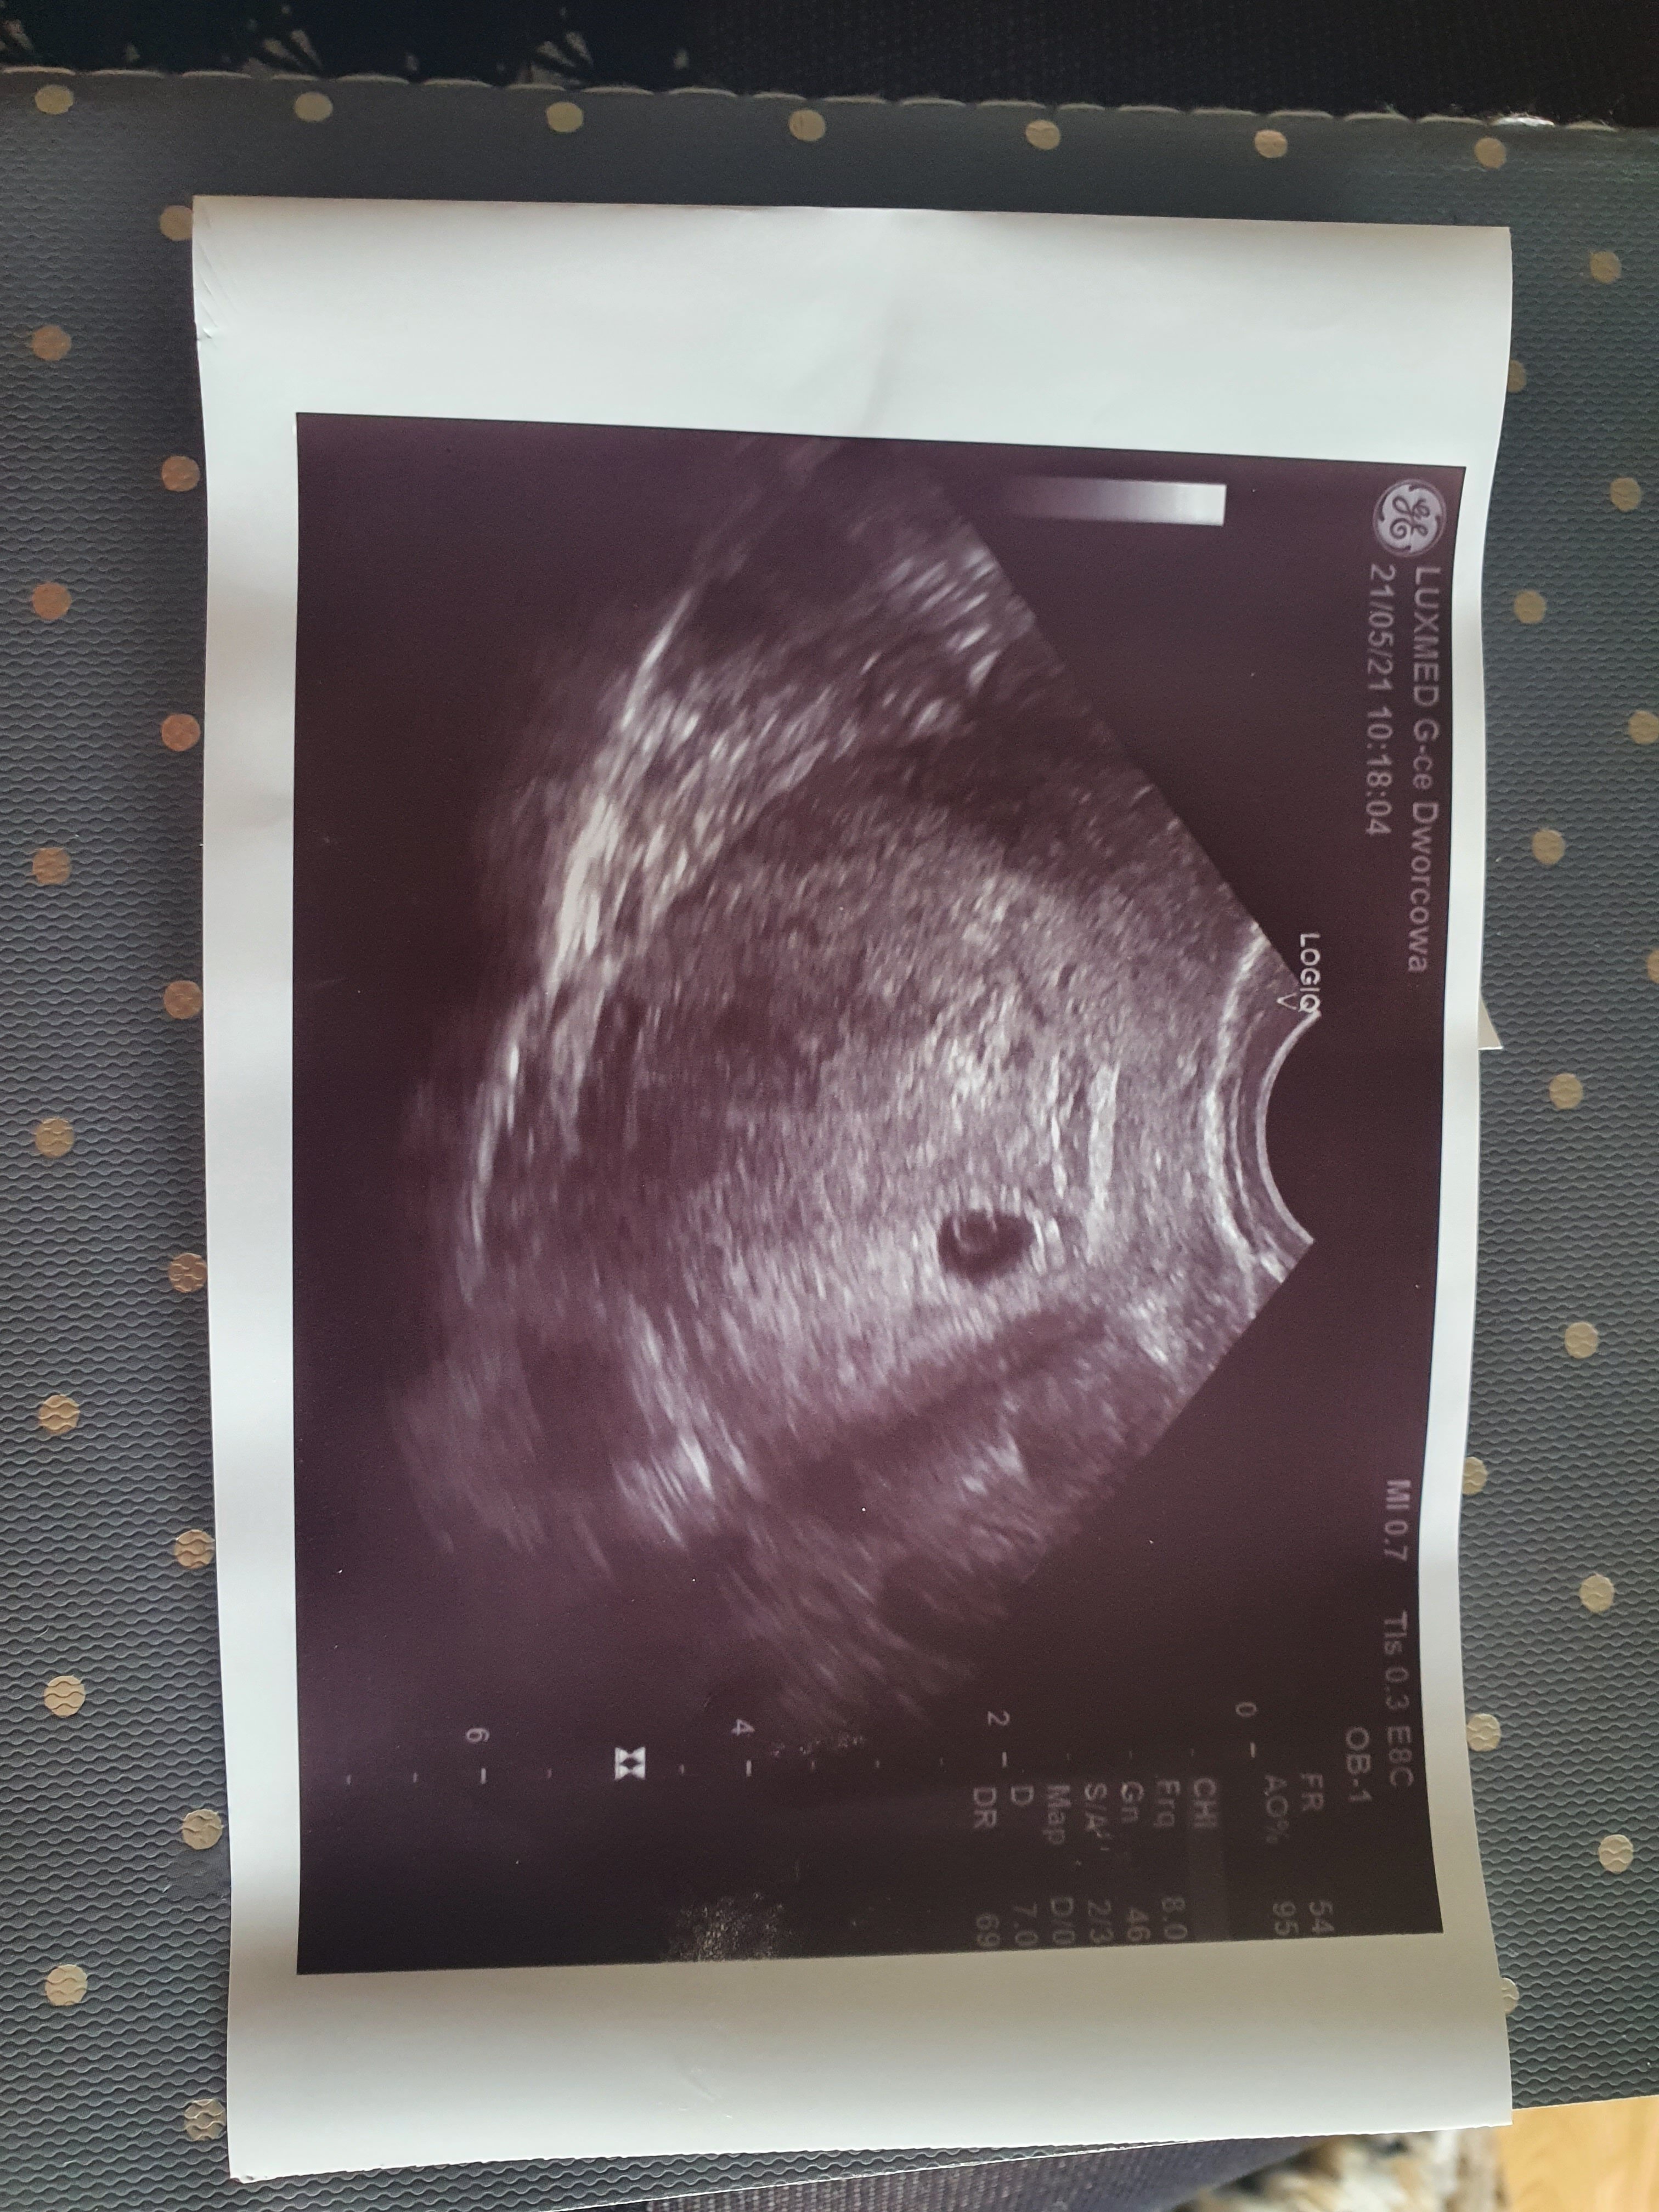

Tez miałam w marcu biochem, nie martw się, biochem to taka selekcja naturalna, skoro teraz jest fasolka i nic się nie dzieje to dobry znak

kiedy masz następną wizytę?

Powiem szczerze, ze mnie wcale nie martwi ten biochem, one są bardzo powszechne i nie wykluczają zdrowej ciąży, przed córką też miałam kilka biochemów, dopiero po paru latach zorientowałam się, ze w nich byłam, wtedy jeszcze myślałam, ze pozytywny test to taki na którym dwie kreski są tego samego koloru

no i jak zaskoczyło to urodziłam zdrową bardzo bystrą córeczkę

teraz tez czuje, ze skoro zaskoczyło to już się udało